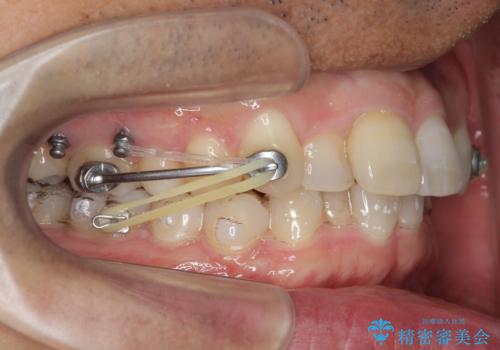

2級ディープバイト 遠心移動を伴うマウスピース矯正

・深い噛み合わせ(ディープバイト) ・2級性の咬合関係(上顎前突)・前歯のがたつき

以上のような歯並びの問題をマウスピース矯正インビザライン・カリエール・マイクロインプラント・部分ワイヤー矯正

を用いて改善していきます。

深い噛み合わせと上顎前突の状態を治すのに時間がかかりましたが、治療後は理想的で安定した咬合関係となりました。